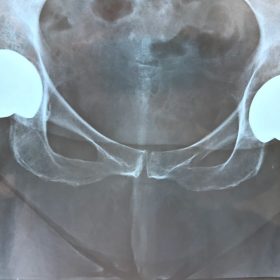

Διάγνωση- Σταδιοποίηση

Διακρίνονται σε 4 στάδια.

Στάδιο Ι. Στένωση του μεσαθριου διαστήματος

Στάδιο ΙΙ. Σκλήρυνση του υποκύμενου χόνδρου

Στάδιο ΙΙΙ. Σκλήρυνση του υπερκείμενου χόνδρου, καταστροφή του υποχόνδρινου οστούν, σχηματισμός οστεόφυτων, οίδημα αρθρώσεως και βραδυνός πόνος

Στάδιο IV. Οστική καθίζηση, καταστροφή μαλακών μορίων μυϊκών ομάδων, υπεξάρθρημα της αρθρώσεως και αλλαγή του μηχανικού άξονα